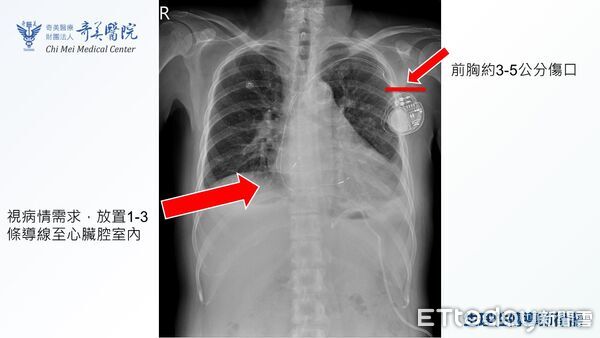

▲置放採用生理性傳導技術的心臟節律器須精準定位,若病人條件適合,可大幅提升治療品質 。(圖/奇美醫院提供)

針對治療,黃沛頡說,心臟節律器置放已有近70年歷史,技術成熟且安全,近年來隨著科技進展,已發展出生理性傳導技術,其模擬心臟天然電路,避免傳統節律器可能造成的心室不同步收縮;根據多項臨床研究,此技術有助減緩心臟功能下降,可降低心房顫動復發風險,部分病人甚至可改善心衰竭症狀。

黃沛頡指出,在20年前,台灣1年接受心臟節律器置放的病人約2千至4千人,近年已增加到7500人左右;因應需求上升,奇美團隊在心室型生理性傳導技術累積經驗後,於去年引進「心房型巴赫曼氏束」生理性傳導節律器,提供更完整的選擇,不過相關手術需精準定位,置放時間會增加0.5至1.5小時,須經醫師縝密評估患者是否適合。